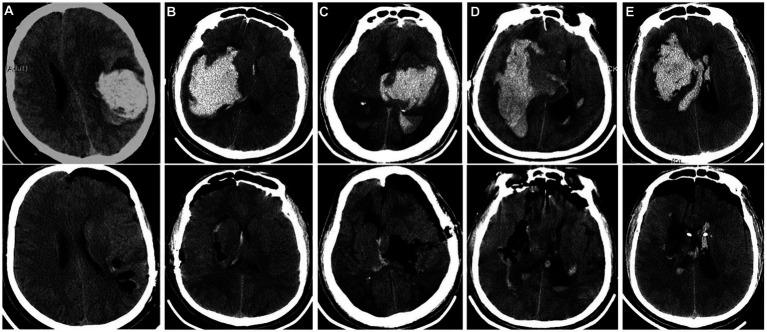

神经内镜手术治疗合并脑疝的高血压脑出血:与开颅手术对比的回顾性研究

Neuroendoscopy surgery for hypertensive intracerebral hemorrhage with concurrent brain herniation: a retrospective study of comparison with craniotomy.

Hypertensive intracerebral hemorrhage combined with cerebral hernia (HIH-CH) is a serious condition. Neuroendoscopy can effectively remove intracranial hematoma, but there is no relevant research support for its utility in patients with HIH-CH. The purpose of this study is to investigate the efficacy and safety of neuroendoscopy in patients with HIH-CH.

Patients with HIH-CH who received craniotomy or neuroendoscopy treatment were included. The patients were divided into craniotomy (CHE) group and neuroendoscopy (NEHE) group. Clinical data and follow-up outcome of the two groups were collected. The primary outcome was hematoma clearance.

The hematoma clearance rate (%) of patients in NEHE group was 97.65 (92.75, 100.00), and that of patients in CHE group was 95.00 (90.00, 100.00), > 0.05. The operation time and intraoperative bleeding volume of patients in NEHE group were significantly less than those in CHE group ( < 0.05). There was no significant difference in the volume of residual hematoma and the incidence of rebleeding between the two groups ( > 0.05). The length of stay in ICU in NEHE group was significantly shorter than that in CHE group ( < 0.05).

Neuroendoscopy can safely and effectively remove the intracranial hematoma in patients with hypertensive intracerebral hemorrhage and cerebral hernia, significantly shorten the operation time, reduce the amount of intraoperative hemorrhage, shorten the ICU stay.